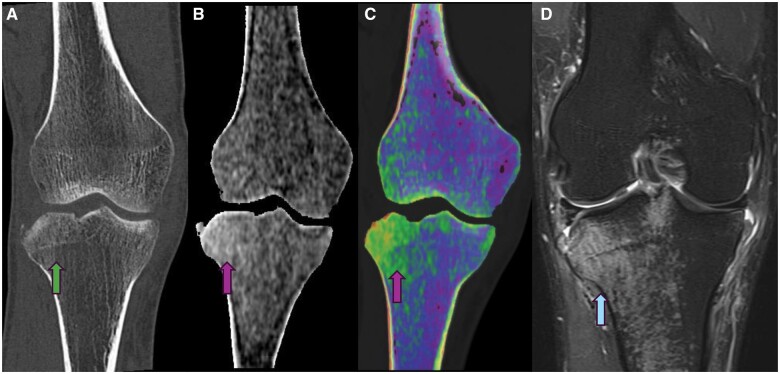

Dual-energy computed tomography (DECT) is an advanced imaging technique that acquires data using two distinct X-ray energy spectra, typically at 80 and 140 kVp, to differentiate materials based on their atomic number and electron density. This capability allows for the enhanced visualisation of various pathologies, including bone marrow oedema (BMO), by providing high-resolution images with notable energy spectral separation while maintaining radiation doses comparable to conventional CT. DECT's ability to create colour-coded virtual non-calcium (VNCa) images has proven particularly valuable in detecting traumatic bone marrow lesions (BMLs) and subtle fractures, offering a reliable alternative or complement to MRI. DECT has emerged as a significant tool in the detection and characterisation of bone marrow pathologies, especially in traumatic injuries. Its ability to generate high-resolution images and distinguish between different tissue types makes it a valuable asset in clinical diagnostics. With its comparable diagnostic accuracy to MRI and the added advantage of reduced examination time and increased availability, DECT represents a promising advancement in the imaging of BMO and related conditions.